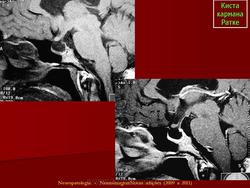

ГМ. Киста кармана Ратке. +

Киста кармана Ратке

Отличные изображения, спасибо. И хорошо что тут стрелочками указана киста и аденогипофиз, который всегда деформирован кистой и киста непосредственно к нему прилижет.

Киста кармана Ратке ИМХО должна иметь стенку. На первой серии снимков верхней стенки нет и киста сливается с супраселлярной цистерной, имеет неотличимые от ликвора сигнальные характеристики. Насчёт подстверждения. Вот интересно мне, как можно подтвердить кисту кармана Ратке в данном случае?? Гистологически?

Мне тоже показалось, что в первой серии изображений кистой и не пахнет.Видится "пустое" турецкое  седло с расширенной  супраселлярной цистерной.Оказалось, что не только мне одной.